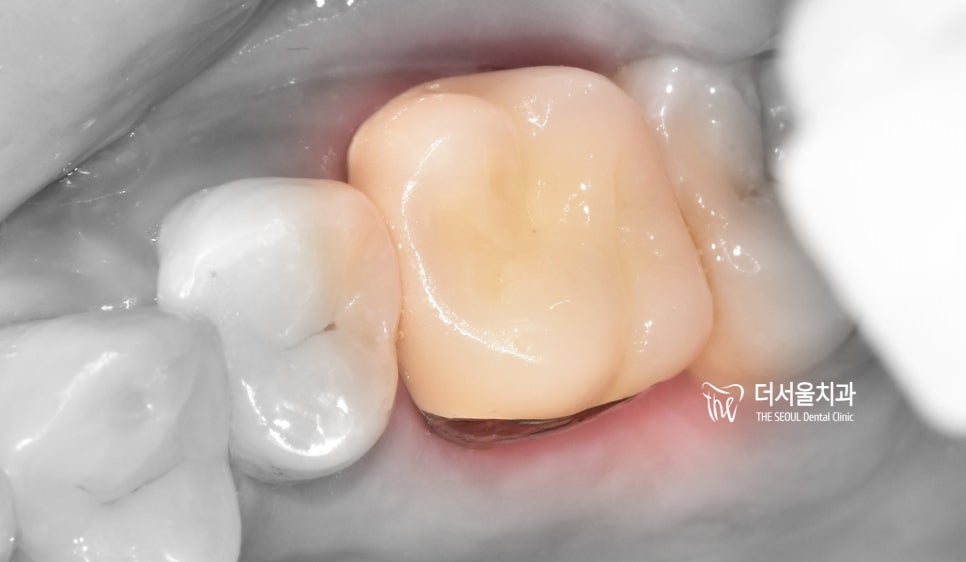

초진 사진을 확인한 결과,

이곳은 심한 충치가 나타나 있던 곳이였습니다.

구강 내를 살펴보면

더욱 확연히 드러나는 것을 알 수 있습니다.

기존 보철 밑으로 심하게 썩어있는 충치와

치아 파절 의 범위를 확인할 수 있네요.

충격이 가해진 곳이 범위가 일부분이라도

이 환자처럼 보철이 씌워져 있는 경우에는

약해진 기존 보철에도 충격이 전달되어

이렇게 큰 손상이 나타날 수 있습니다.